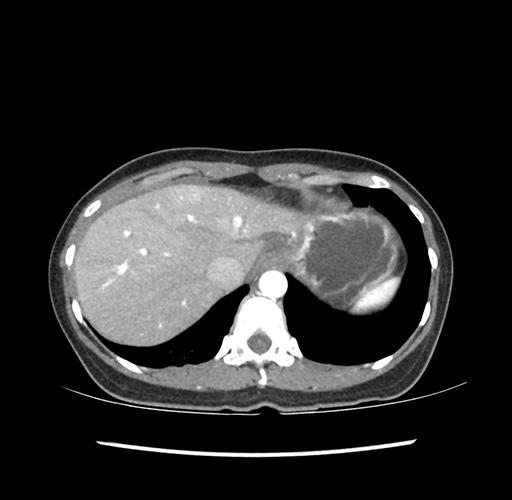

Imaging Analysis

Look through the patient's CT scan to identify any areas of concern for the necessary procedure.

Based on your CT findings, which issue(s) would give reason for "planned slowing down moment(s)" in this case?

Considering a standard left lateral sectionectomy procedure, what step(s) of the operation would you do differently in this case ?